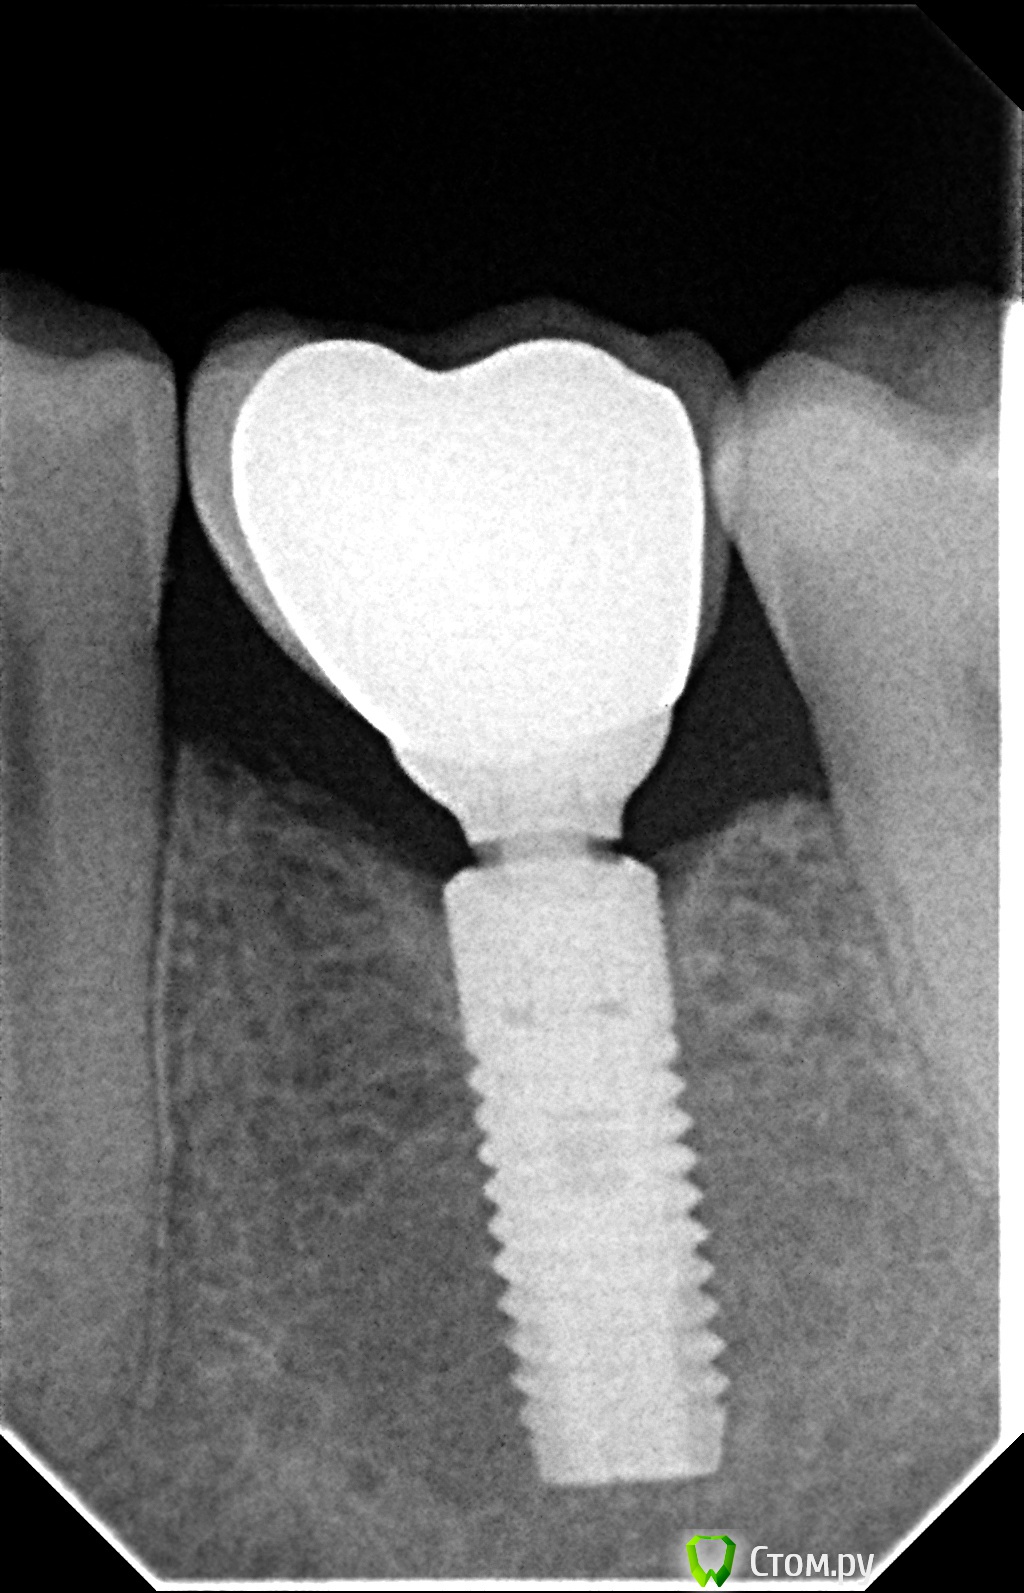

vinstom Опубликовано 25 мая, 2014 Автор Поделиться Опубликовано 25 мая, 2014 Может это поможет в споре. Покопался в истории нашел ОРТО за 2012 год. Т.е. три года, после нагрузки. Можно сравнить ситуацию, очень наглядно. 1 Ссылка на комментарий

Bobby Опубликовано 25 мая, 2014 Поделиться Опубликовано 25 мая, 2014 Может это поможет в споре. Покопался в истории нашел ОРТО за 2012 год. Т.е. три года, после нагрузки. Можно сравнить ситуацию, очень наглядно.Доктор, аккуратно работаете. Красиво. Спасибо за снимок. Ссылка на комментарий

Doc Опубликовано 25 мая, 2014 Поделиться Опубликовано 25 мая, 2014 Кстати, для пяти лет функционирования (топикстартер указал 2009 год, как дату фиксации) на том же Нобеле, подобная ремоделировка вообще является нормой. Вспомним пресловутые 1,5 мм в первый год и 0,2-0,5 каждый последующий. Если на Астре через пять лет и три недели перелома ремоделировка достигла того уровня, который у большинства других систем считается нормой, то это далеко не самый плохой результат. Хотя, конечно, один клинический случай ничего не доказывает. 1 Ссылка на комментарий